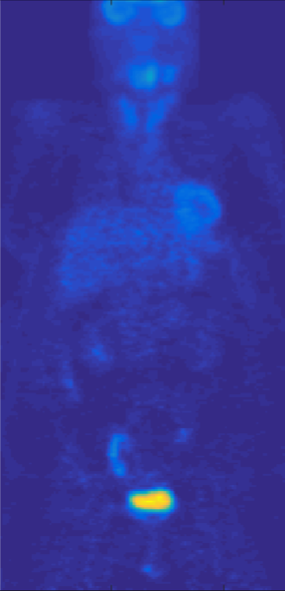

For evaluation, we use three different datasets: a) 58 whole body PET scans of resolution . We randomly pick 10 whole body volumes for testing and train with the 48 remaining volumes. We normalize the intensity range of our training and testing volumes using the min-max method based on min and max intensity values of the whole training set. Next, in both training and testing, each single sub-volume is also normalized to using its min and max before feeding it into network. b) 958 MRI prostate scans of different resolution which were resampled to voxel size of . We randomly picked 258 volumes for testing, and train with remaining 700 volumes. c) hlUltrasound echocardiography images of resolution , used for left ventricular myocardial segmentation, were split into 430 train and 20 test. The datasets were collected internally and from The Cancer Imaging Archive (TCIA) QIN-HEADNECK and ProstateX datasets [26, 27, 28, 29, 30]. Samples of the three datasets are shown in Fig. 2.

Over all the organs, Dice scores for the proposed method (proposed architecture + Combo loss) ranges from to . We show the worst, an in-between and the best results in terms of Dice score in Fig. 5. Although the left case in the figure seems to be the worst result in terms of Dice score, it is a difficult case with several missing organs. However, the proposed method has been able to handle multiple missing organs to a high extent. Note that some organs c an be physically absent from a patient body, as in renal agenesis or radical (complete) nephrectomy, but in PET scans, there might be more ”missing” organs (similar to the left case in Fig. 5) simply because of lack of radiotracer uptake in these organs thus they do not appear in PET. Although, in training, Dice score improvement compared to 3D V-Net is small, as shown in Figure 4, in test, proposed loss helped 3D V-Net in terms of reducing organ misclassification and false positives. Looking at both Table III and Fig. 4, 3D U-Net and 3D SegNet achieved higher performance when incorporating the proposed loss.